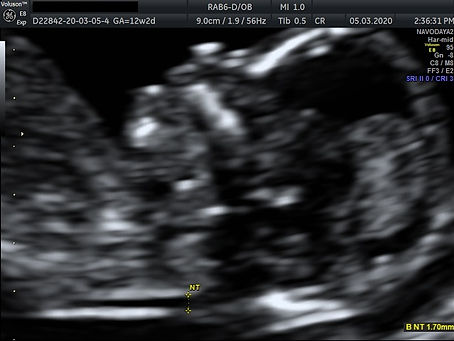

Ultrasound

This Ultrasound scan is called Nuchal Translucency scan (NT Scan). Nuchal Translucency is the name for the fluid behind the neck of a fetus. An NT scan uses ultrasound to measure the amount of fluid. The fluid under the skin at the back of the baby's neck appears "black" on ultrasound images and is normally present in all fetuses in early pregnancy. A fetus at risk of Down's syndrome tends to have a higher amount of fluid. The thickness of the fluid can predict whether the early fetus may have Down syndrome or a number of other chromosomal abnormalities. It is essential that the Nuchal Scan is performed between the 11th and 14th week of pregnancy, because the accuracy is best in this period.